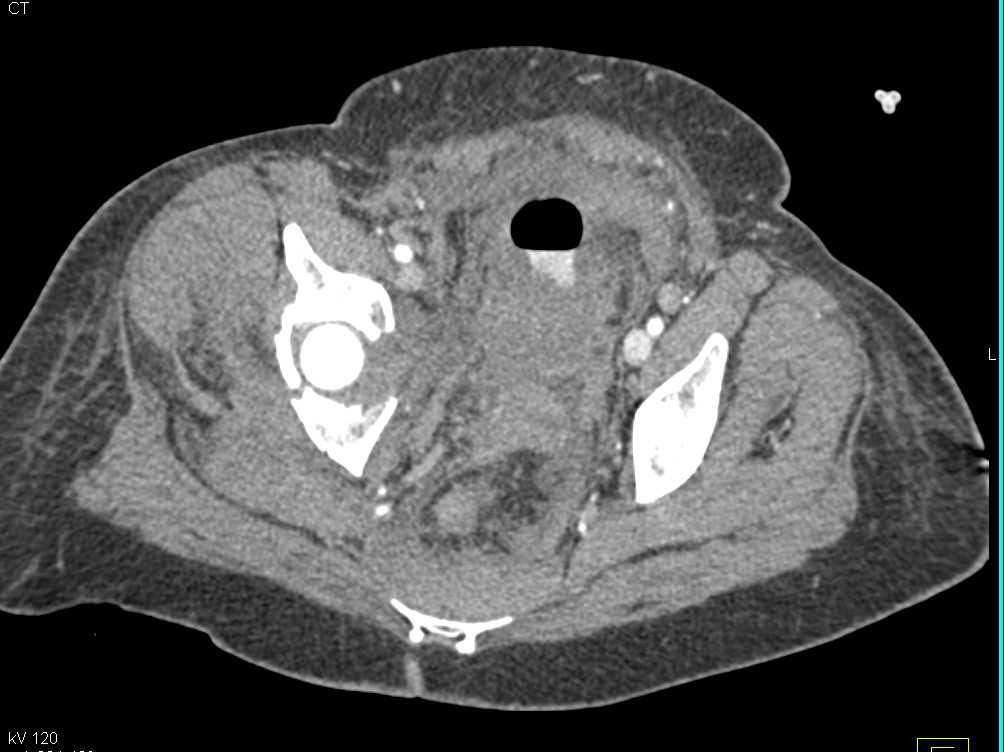

Left Psoas Abscess as a Consequence of Pancreatitis